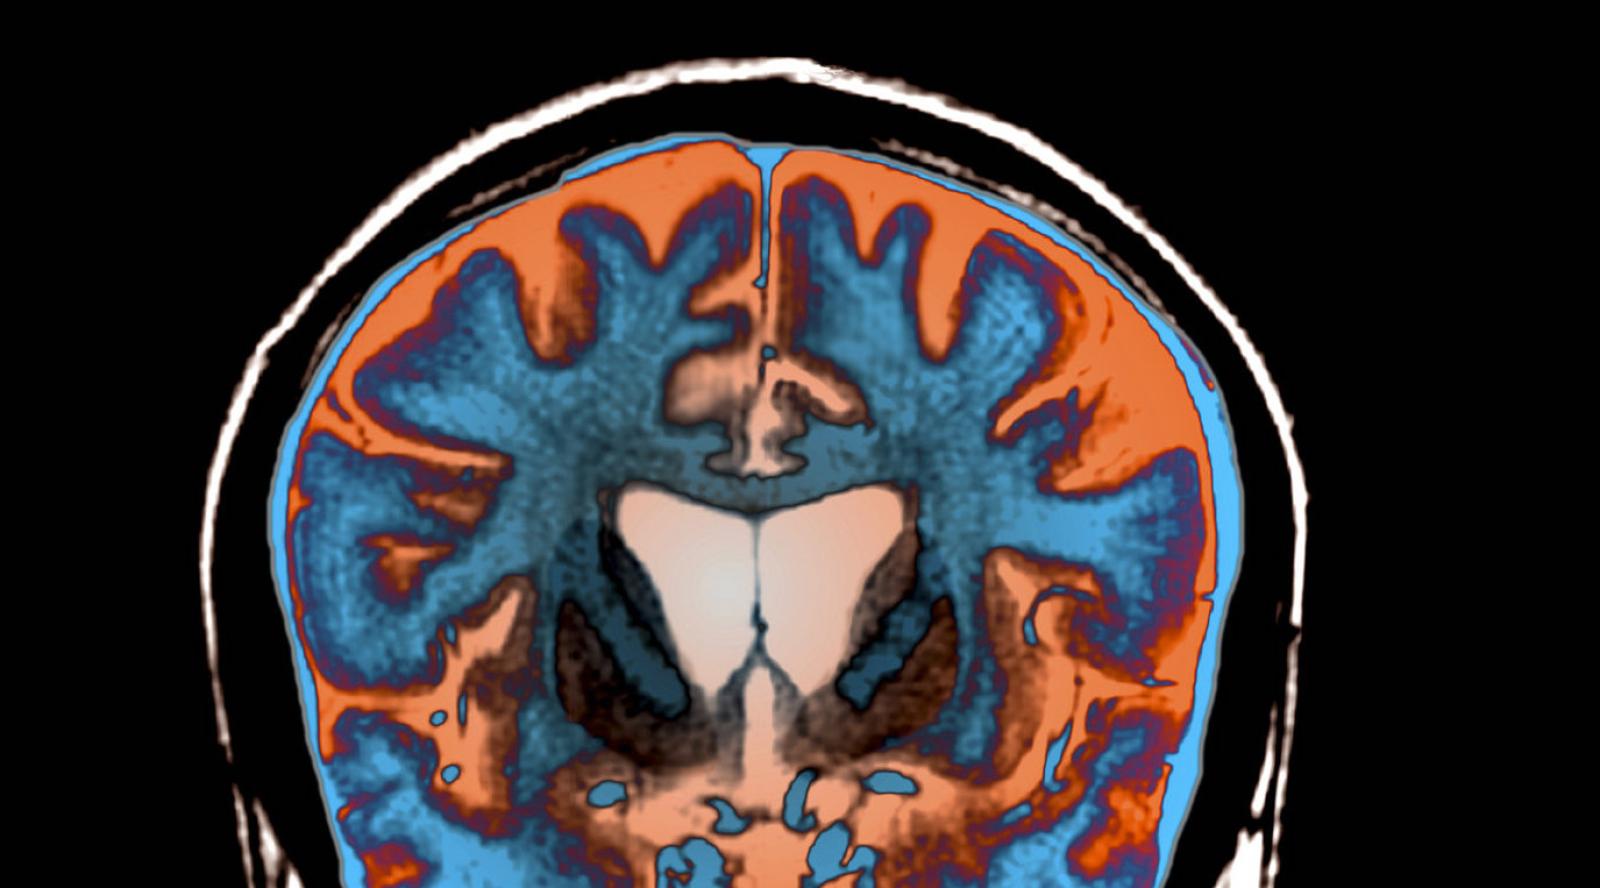

An MRI scan shows signs of atrophy in the brain of a patient with Huntington's disease.

Science Photo Library/Science Source